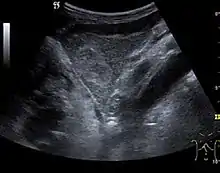

Liver cysts

They can be single or multiple, with variable size, generally less than 20 mm (congenital). Rarely, sizes can reach several centimeters, leading up to the substitution of a whole liver lobe (acquired, parasitic). They may be associated with renal cysts; in this case the disease has a hereditary, autosomal dominant transmission (von Hippel Lindau disease).

The ultrasound appearance is a well defined lesion, with very thin, almost unapparent walls, without circulatory signal at Doppler or CEUS investigation. The content is transonic suggesting fluid composition. The presence of membranes, abundant sediment or cysts inside is suggestive for parasitic, hydatid nature. Posterior from the lesion the acoustic enhancement phenomenon is seen, which strengthens the suspicion of fluid mass. They typically displace normal liver vessels but no vascular or biliary invasion occurs.